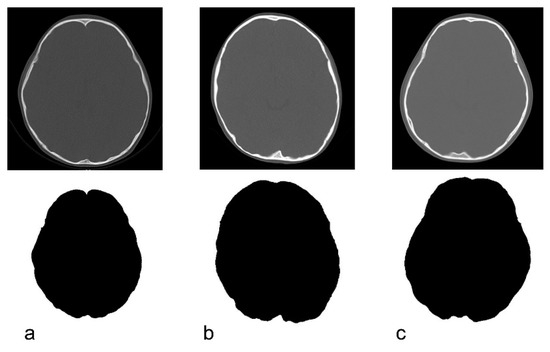

2.3. Image Processing Method for CT Data